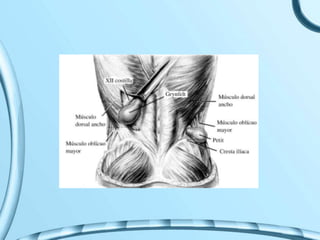

TRIANGULO DE LEAN LOUS

PETIT

CUADRILATERO LUMBAR

O DE GRYNFELT

Cuadrilátero de Grynfelt, lado izquierdo 1. 12.a costilla; 2. aponeurosis transversa; 3. nervio

iliohipogástrico; 4. músculo oblicuo interno; 5. cresta ilíaca; 6. músculo dorsal ancho.